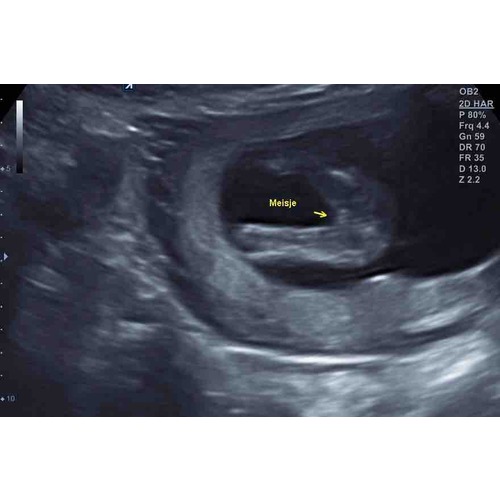

Ik heb ook die streepjes. Maar de nub van jen2e foto zou ik al zeggen dat jongen is🙈 maar nu weet nog niemand zeker of jullie een zoon of dochter krijgen?

Hier de 3 streepjes bij 15 weken en 3 dagen